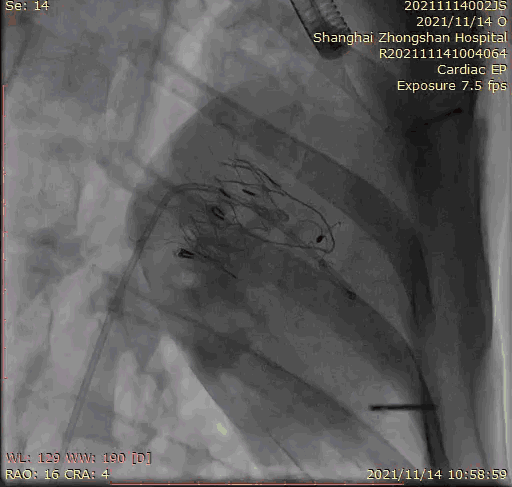

上海中山醫(yī)院葛均波院士、錢(qián)菊英院長(zhǎng)、周達(dá)新教授、潘文志教授、潘翠珍教授、李偉教授共同完成此次臨床前研究。術(shù)后葛均波院士對(duì)Lux-Valve Plus的器械操作性能給予了高度評(píng)價(jià),DSA和超聲影像也顯示出在本次研究中Lux-Valve Plus的安全性和有效性俱佳。

本次臨床前研究經(jīng)右側(cè)頸靜脈置入LuX-Valve Plus輸送系統(tǒng)可調(diào)彎鞘管,在DSA及超聲引導(dǎo)下將人工三尖瓣瓣膜植入到原有三尖瓣位置,利用獨(dú)特的錨定技術(shù)將人工瓣膜支架可靠固定在預(yù)定的位置。